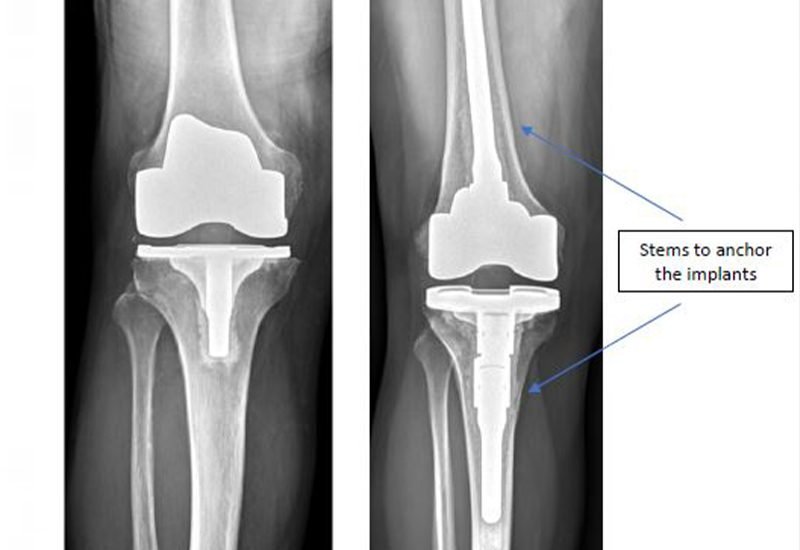

- X-rays: Are able to tell the degree of degeneration of the joint, bone damage, or arthritis vividly and accurately.

- Customized Implant Selection: Our implants are based on your body form, age and also activity level.

- Computer-Navigated Precision: We will have computer assistance to ensure that the implant is placed in an optimal stance to ensure good joint functioning.